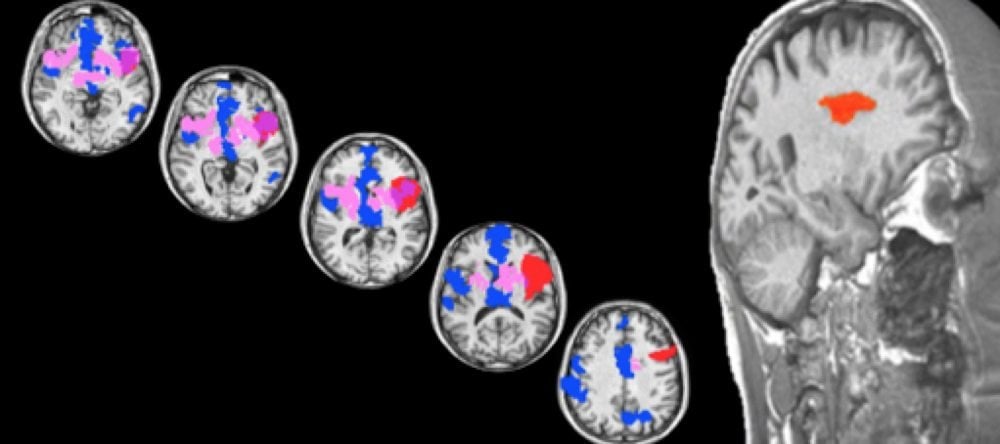

In the earlier paper, “The Common Neural Bases Between Sexual Desire and Love: A Multilevel Kernel Density fMRI Analysis,” Cacioppo and colleagues examined a number of studies of brain scans that looked at differences between love and lust.

The studies showed consistently that the anterior insula was associated with love, and the posterior insula was associated with lust. However, as in all fMRI studies, the findings were correlational.

Image Source: The image is credited to Chris Frum and James Lewis/West Virginia University; Robin Weiss/University of Chicago and is adapted from the University of Chicago press release.